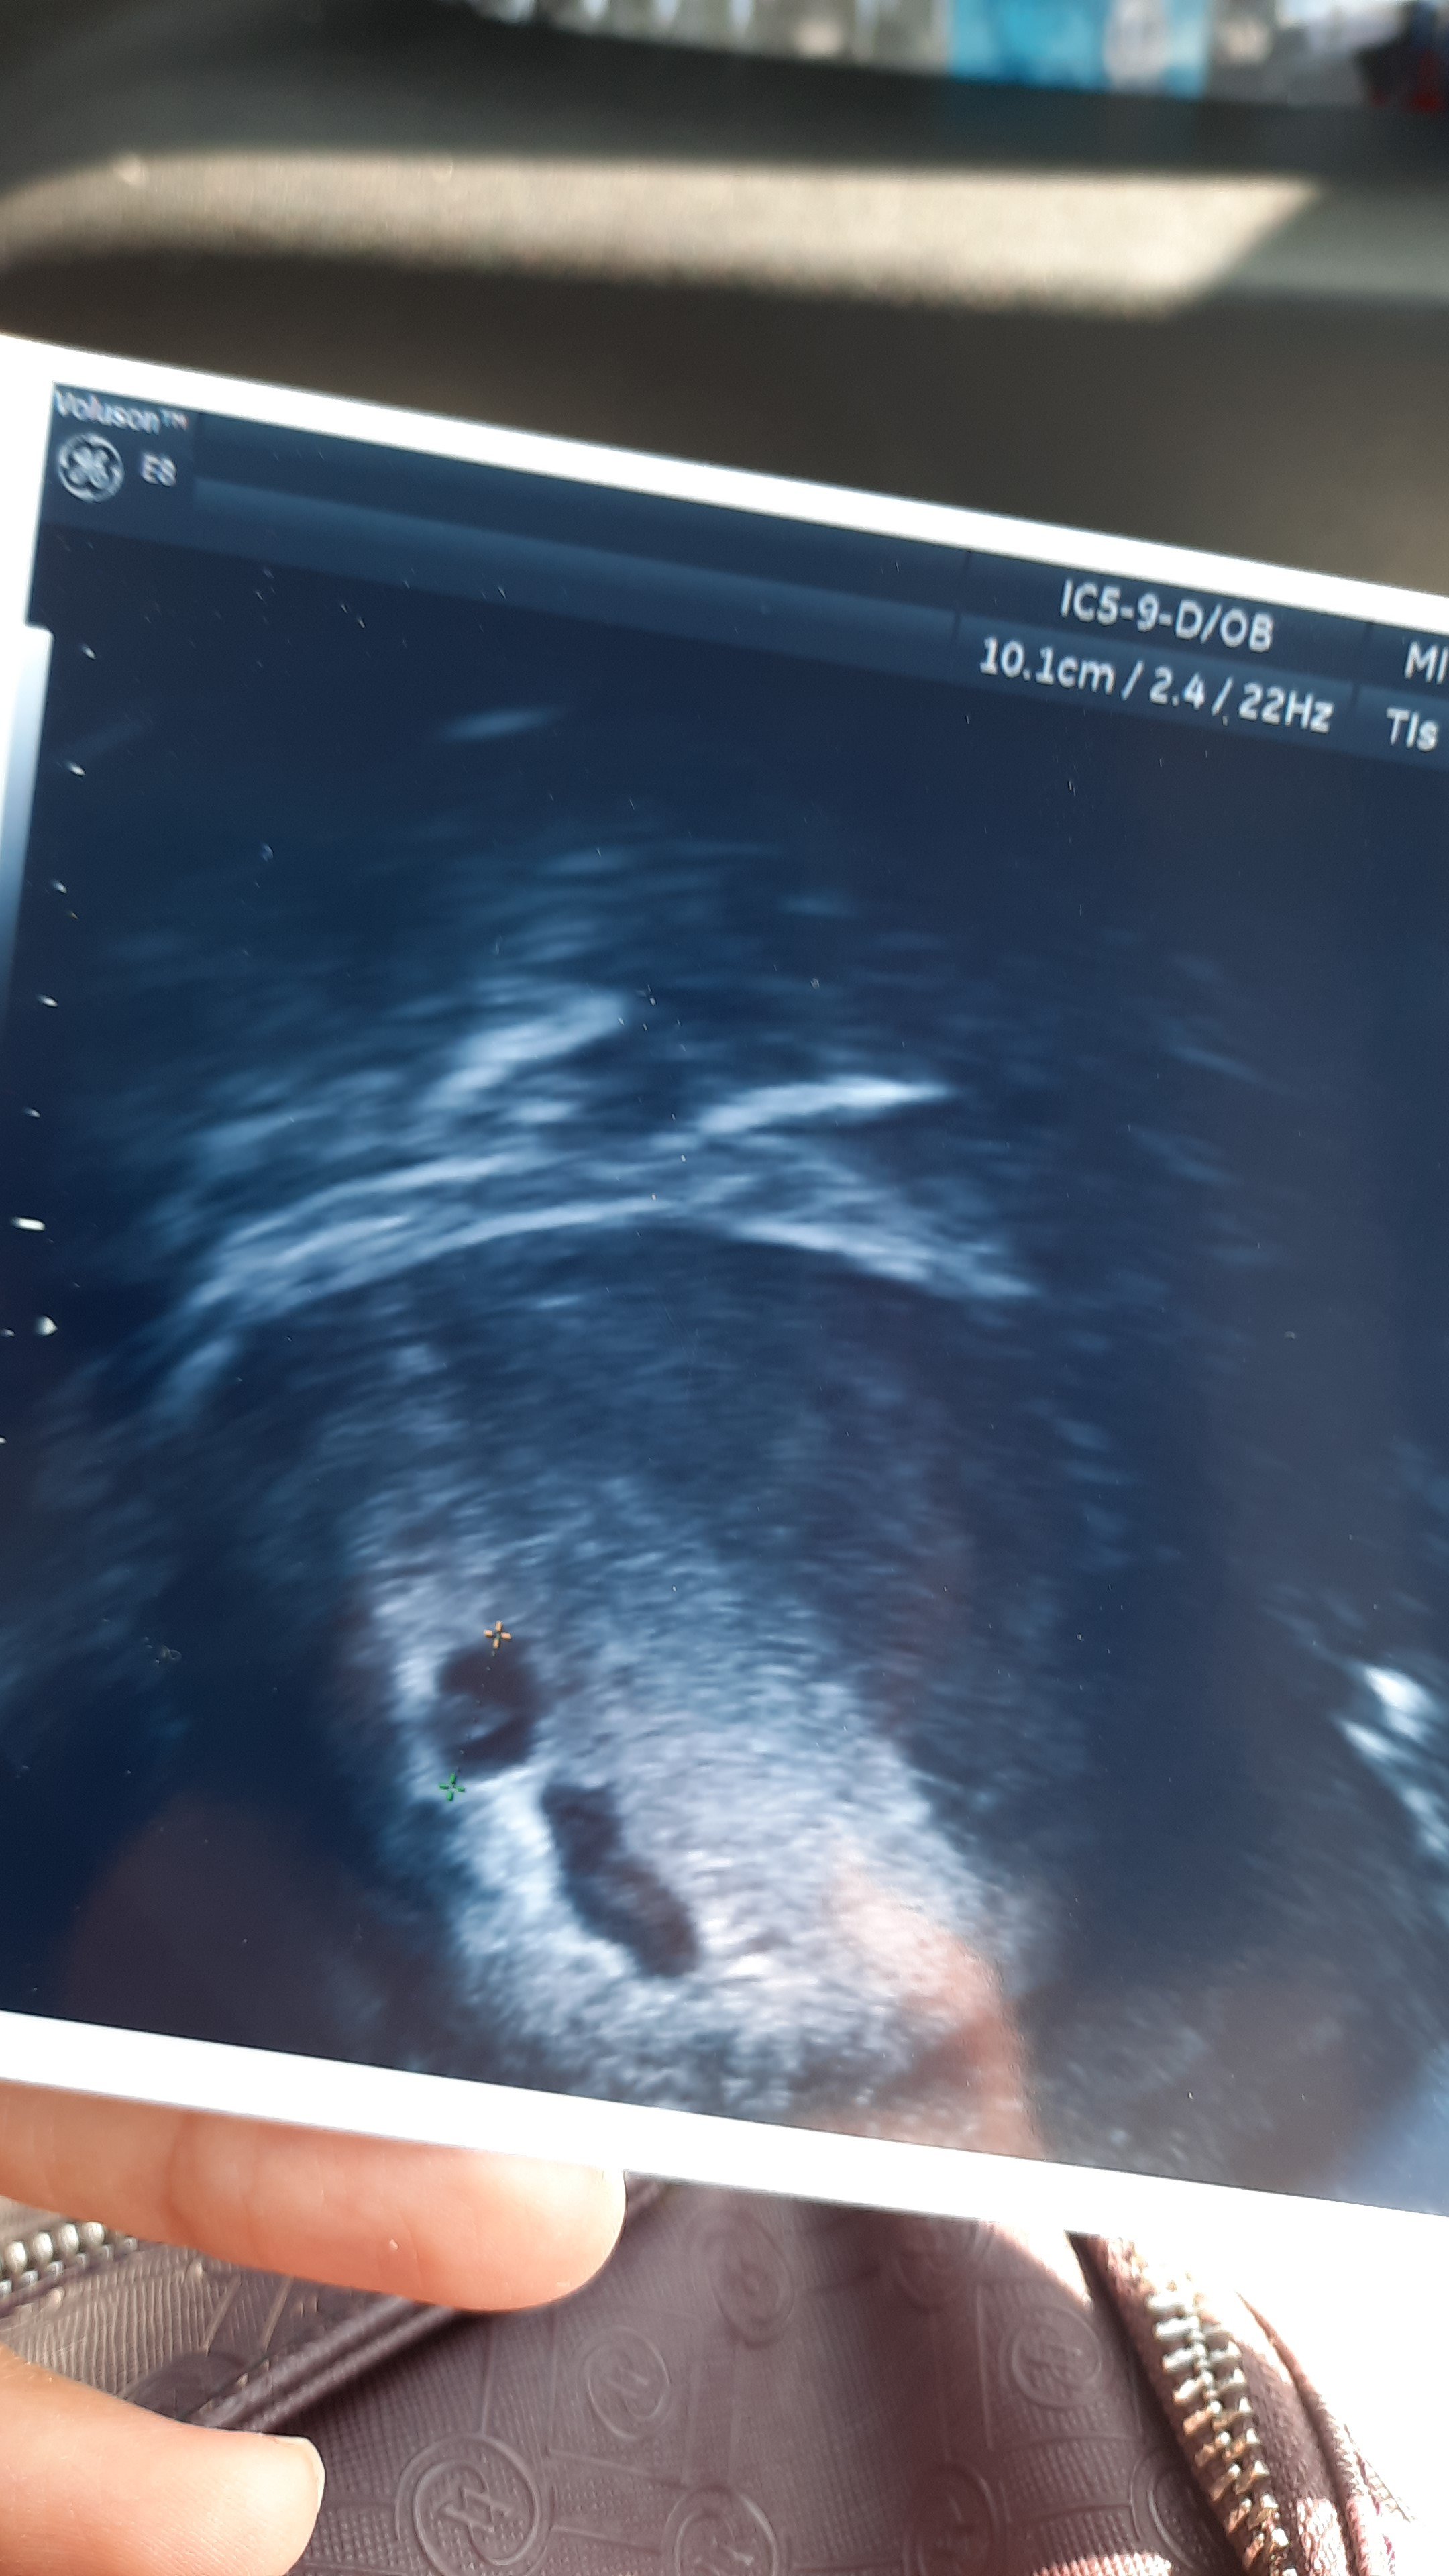

İnsanllah cnm herşey gönlünce olur Allah inşallah saglikla kucağına almayi nasip eder benmde ultrasyon resmin şöyle 5+4 haftayken normal mi

Alta bir ok var orda beyaz birşey var oda yuvarlak gibi o nedir bilmiyorum bile doktor bilgilendirmedi devlet olduğu için 7 haftalık oraya gidicm tekrardan daha gitmiycm oraya yolk kesesi mi acaba o

Evet göbekten baktrdm cnm yuvarlak olan varya o artı konulmuş 4+6 gitmiştim 5+4 haftalık olduğumu öğrenmistm orda